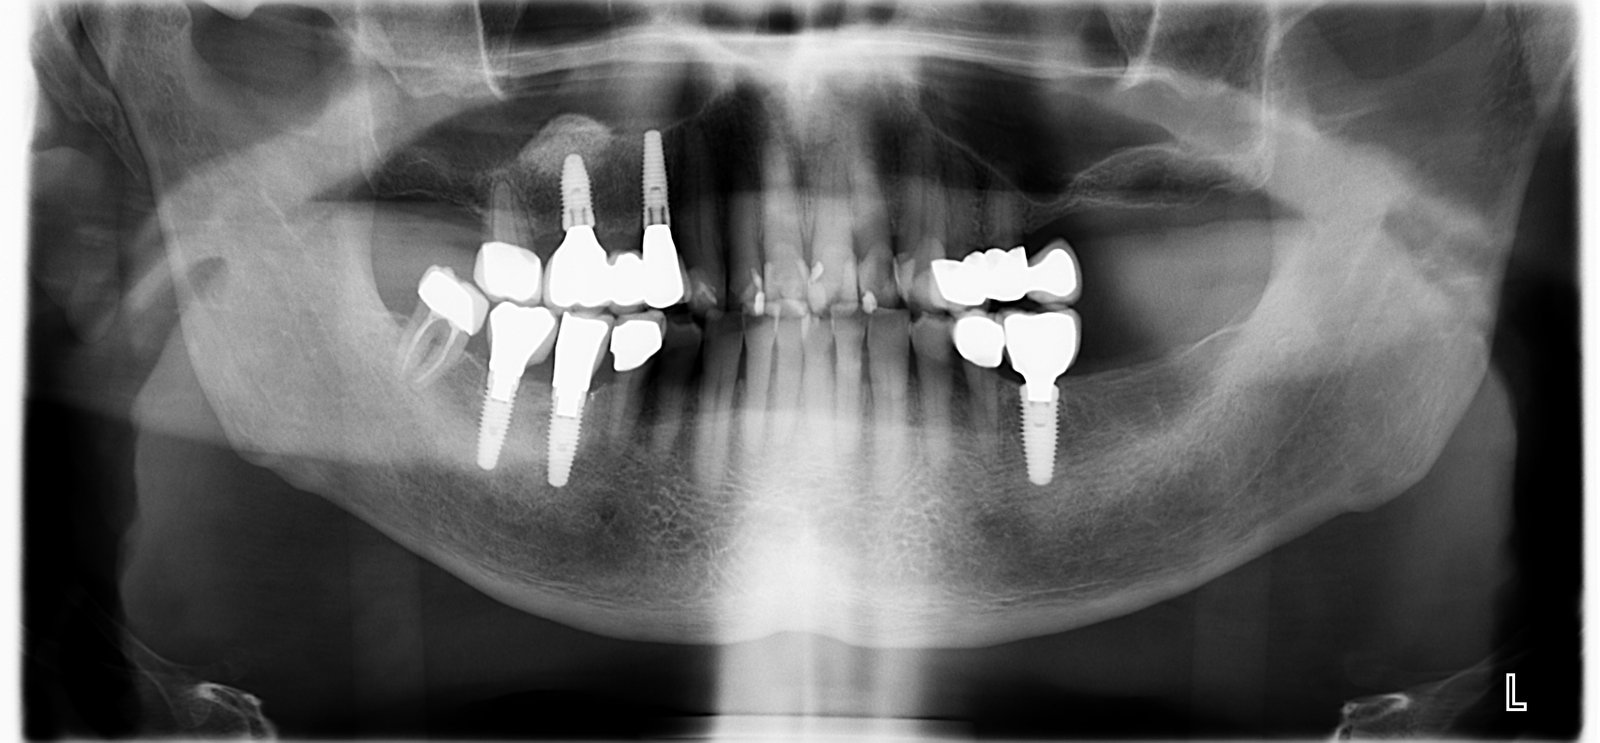

Hola Envie el caso de esta Paciente respecto un implante del 37 hace unos dias. Resulta que la misma Pacientes solicito una solucion en el Maxilar superior y la Paciente [...]